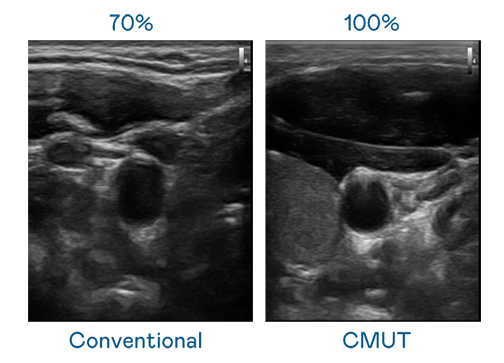

CMUT 技术是一种用电容式微机电元件来产生超音波讯号的技术。与传统 PZT 压电式技术相比,CMUT 频宽增加 30%,更宽频的超音波讯号让影像解析度大幅提升,是实现高影像品质医疗超音波扫描、促进精准医疗发展的关键技术。

超音波影像的解析度高低,首先取决于探头能发出的讯号频宽。乐竞官网登录入口 CMUT 可提供高清晰的超音波讯号,提供高频宽、高灵敏度、影像纹理细节更高的超音波影像,协助医护人员缩短影像判读时间及利用精准的医疗影像进行诊断。